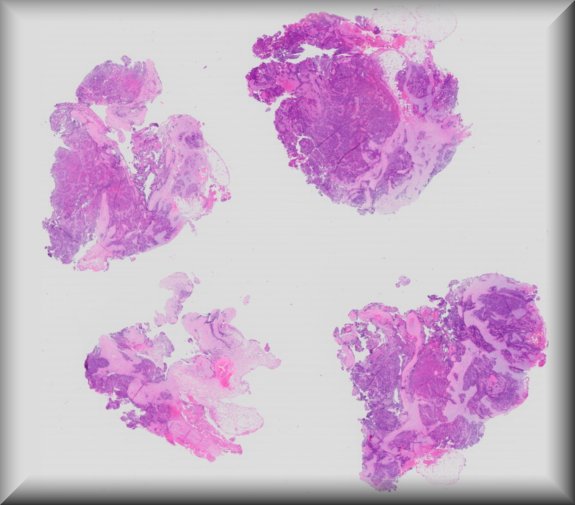

Patricia Chévez Barrios (Houston): 2 year-old-boy with history of group D unilateral retinoblastoma s/p systemic chemotherapy, cryotherapy and intravirteous chemotherapy. Enucleated for progressive disease. |